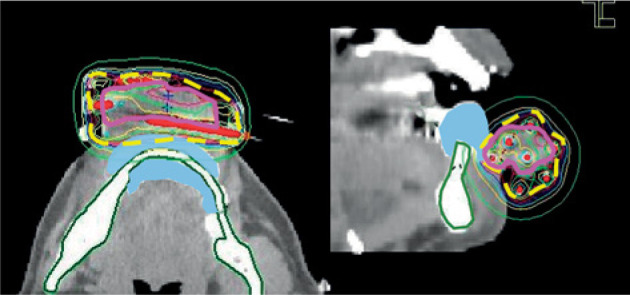

Material and methods: Patients with localized lower lip cancer, who received IG HDR-BT with custom-made surface applicators as monotherapy at the NHO Osaka National Hospital between February 2012 and January 2015 were enrolled in this study. One to three applicators were implanted interstitially, and two to six were placed on tumor surface. Planning-aimed dose (PAD) was 54 Gy, 48 Gy for a recurrent case, and irradiation was delivered at 6 Gy/fraction, twice a day. Dosimetric goal was to achieve D90: clinical target volume (CTV) > PAD without excessive dose to the mandible. A lead shield was placed between the gingiva and lower lip during irradiation to reduce the dose to the mandible in all but one edentulous patient. A gauze with 2% lidocaine was inserted intra-orally to reduce the dose to the upper lip and maxilla.

Results: Six patients (T1 : T2 : T3 = 3 : 2 : 1), including one recurrent case, were enrolled in this study. The CTV was contoured on computed tomography and in two cases, magnetic resonance imaging was used as a reference for contouring. The median follow-up was 69.5 months. The primary tumor was controlled in all cases. No serious late adverse reactions were observed. The median D90 (CTV) and V100 (PAD) were 108.9% PAD and 99.3% CTV, respectively. The median D0.1cm3 (mandible) was 3.2 Gy per fraction.

Conclusions: IG HDR-BT with custom-made surface applicators for lower lip cancer as monotherapy showed an excellent CTV dose and acceptable doses to the mandible, with good long-term clinical results.